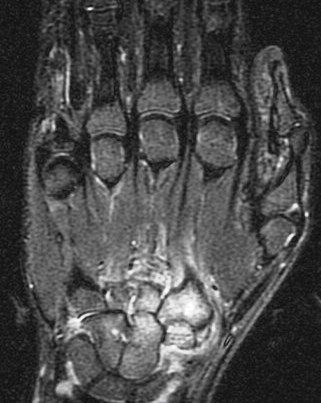

14 y/o with history of bilateral wrist pain.

His carries a known diagnosis of Juvenile Rheumatoid Arthritis. (RID3610) New term is JIA. He has failed steroid therapy and methotrexate. Currently on humira. R/O osseous change. Its ruled in. Reference article.

Juvenile idiopathic arthritis